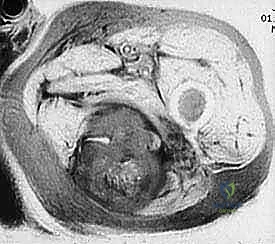

2. ساركوما الأنسجة الرخوة (Soft Tissue Sarcomas)

تنشأ في الأنسجة الداعمة المحيطة بالعظام. تشمل:

* ساركوما الخلايا الزليليّة (Synovial Sarcoma).

* الساركوما الشحمية (Liposarcoma).

* الساركوما العضلية الملساء (Leiomyosarcoma).

تتميز هذه الأورام بقدرتها على اختراق الأنسجة المجاورة وتكوين ما يُعرف بـ "المنطقة التفاعلية" (Reactive Zone) أو الكبسولة الكاذبة، والتي تحتوي غالباً على خلايا سرطانية مجهرية. هذا المفهوم البيولوجي هو ما يوجه الدكتور محمد هطيف في تحديد مدى الاستئصال الجراحي.